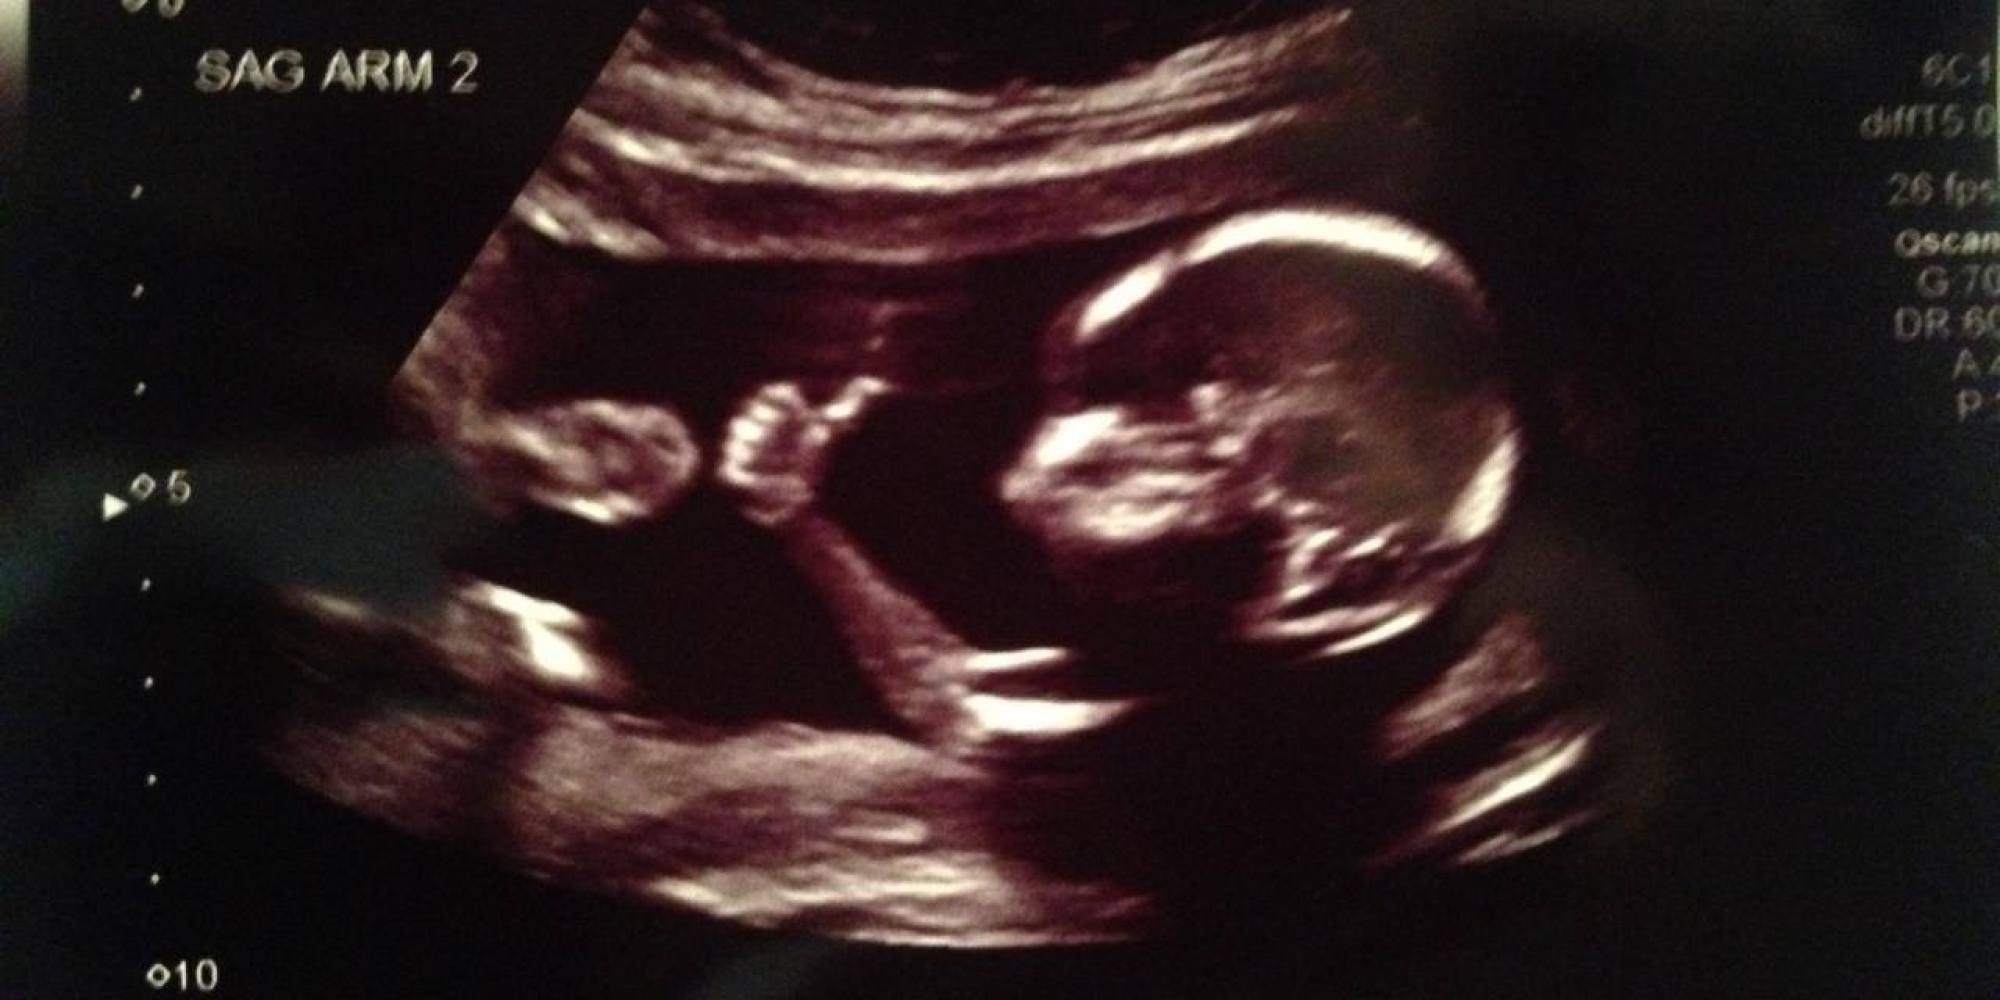

Naše redakce se tento rok dočká roztomilého přírůstku, a tak se nemůžete divit, že nás přepadla miminkovská nálada. Úplně první podobu miminka vidí rodiče přes ultrazvuk, ať už je to ten klasický, nebo moderní 3D verze. Je pravda, že rozpoznat určité detaily je často těžké. Někdy se dokonce zdá, že miminka si z nás dělají legraci nebo se podobají úplně něčemu/někomu jinému.

Říká se tomu pareidolie. Je to psychologický jev, při němž dochází k dotváření vnímaných neurčitých nebo nezřetelných podnětů ve smysluplné obrazy za pomoci fantazie.

Vědecké vysvětlení ale následujícím ultrazvukům neubírá nic na jejich vtipnosti a zajímavosti.

Tyhle těhotenské ultrazvuky nás baví!